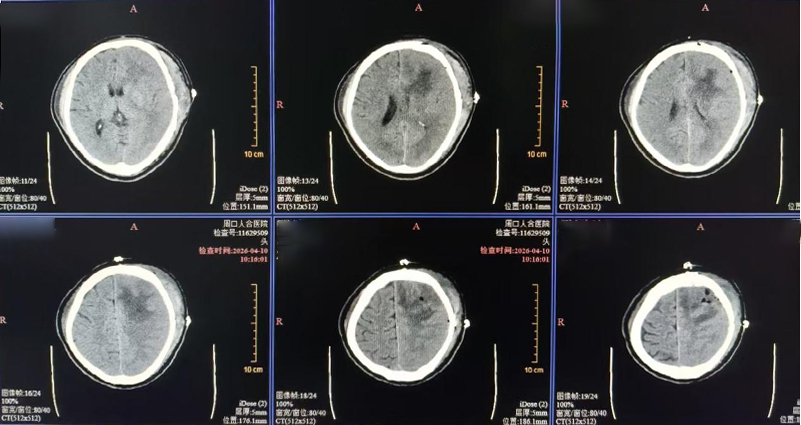

术后24小时复查CT显示血肿清除满意,中线复位;72小时成功拔管,术后1周转回普通病房。病理回示低级别少突胶质细胞瘤,组织学分级2级,目前患者神志清、活动沟通自如,正接受后续放化疗。

术后检查